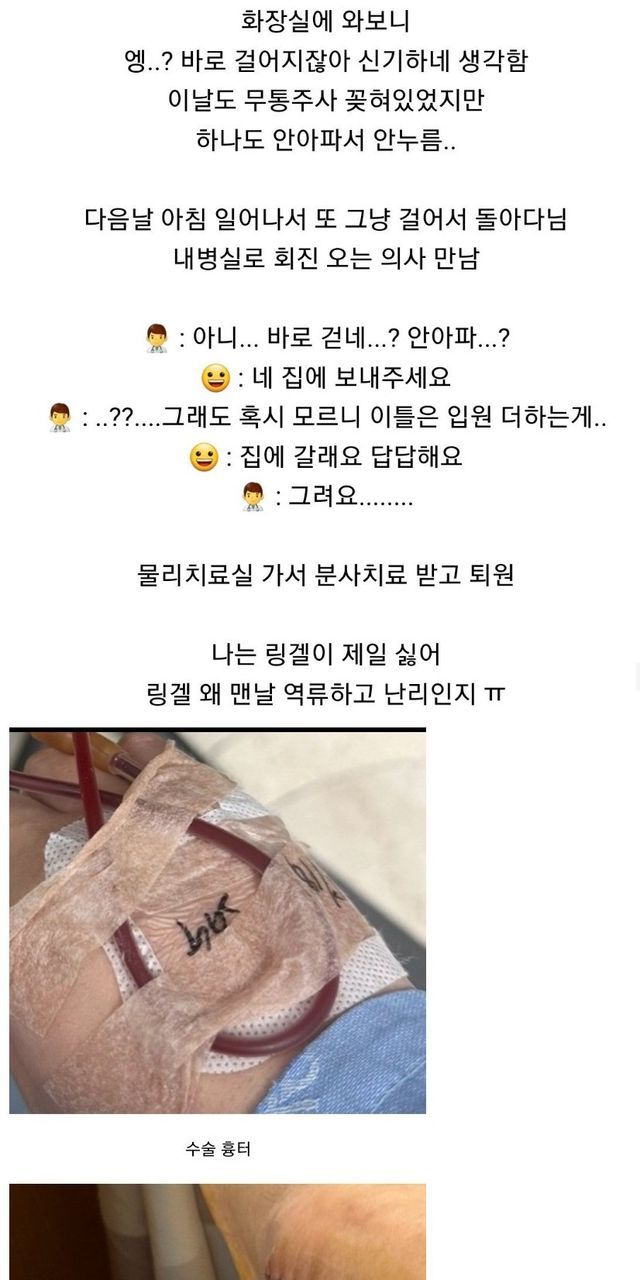

다음날 걸어다니는거 보고 의사 또 화들짝 바로 퇴원함

몸 인증도 했는데 자기 운동 좋아해서 다양하게 한다고 함